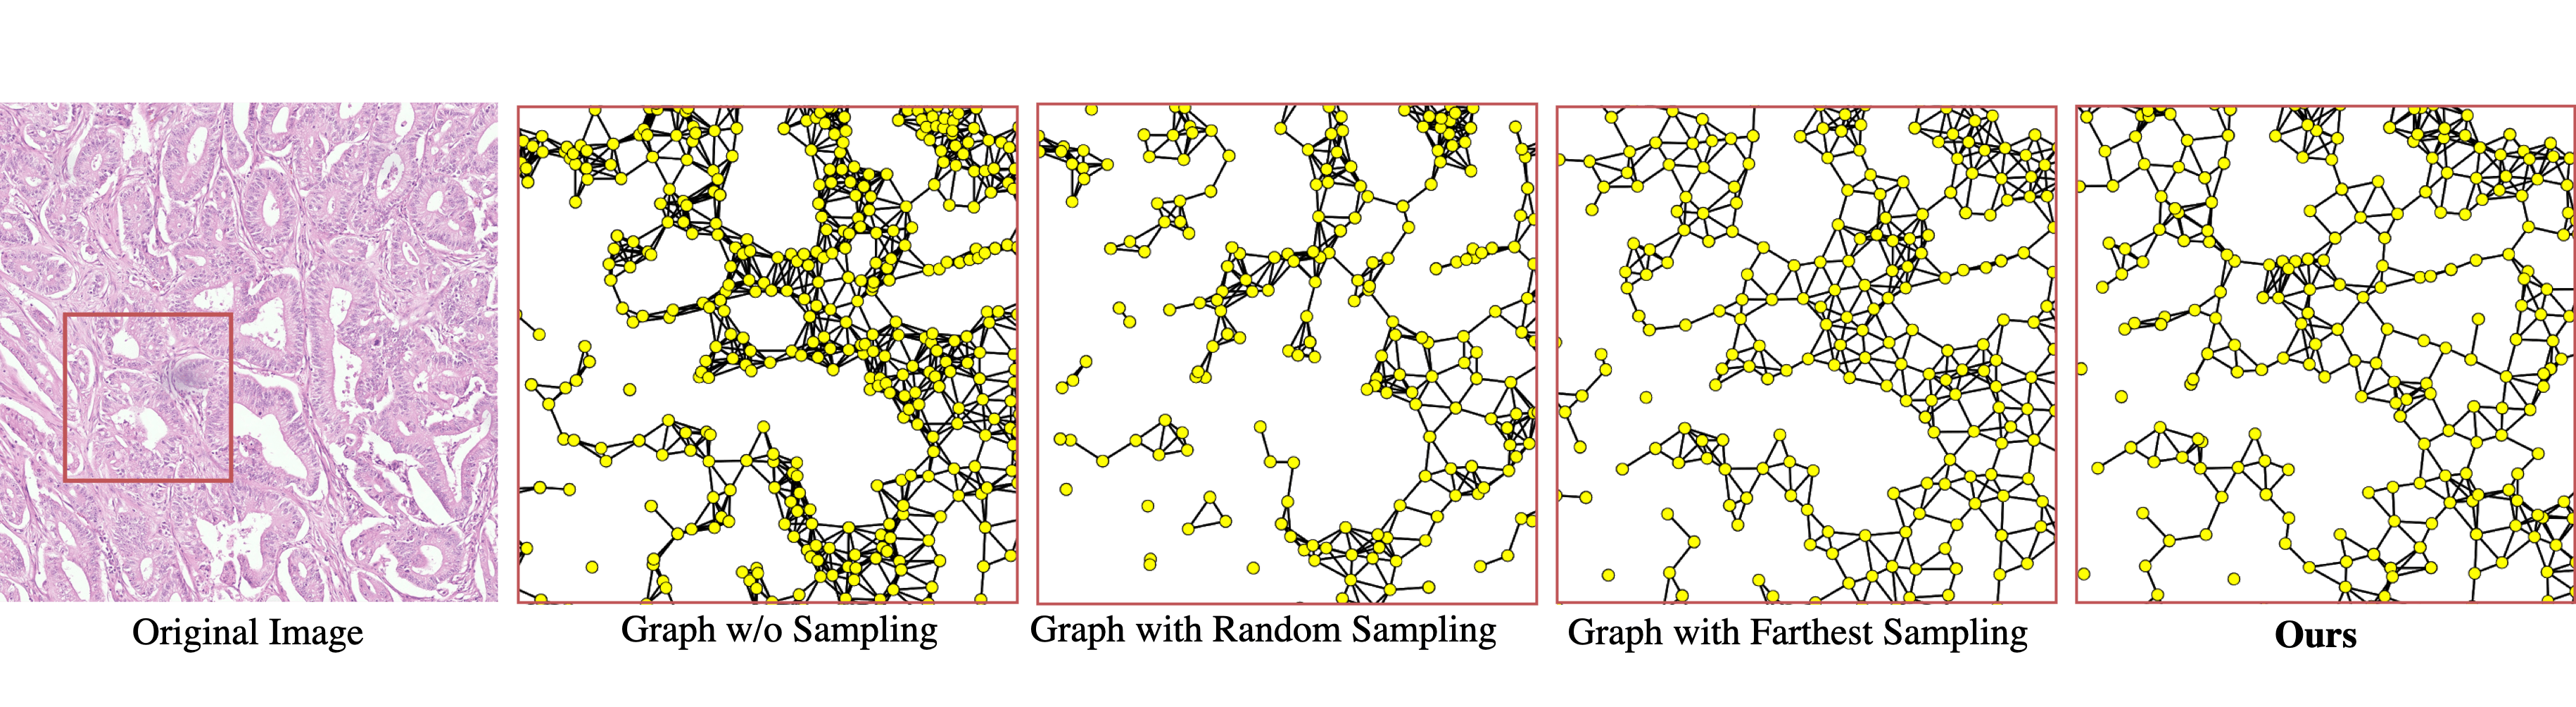

Figure 5: Comparison of different node sampling strategies.

Nuclei sampling strategy: As introduced in Section 3.2, to reduce the size of the cell graph and preserve the cell architecture information in the graph, we propose a representative nuclei sampling strategy. Experiments of utilizing different sample strategy can be seen in Table 1, where Random, Farthest and Fuse denote the random sampling, farthest sampling and our proposed sampling method. Compared with results from random sampling in the second row, using farthest sampling achieves improvement from 88.11%percent88.1188.11\% to 89.47%percent89.4789.47\% for the patch accuracy, as well as the image accuracy from 93.25%percent93.2593.25\% to 96.28%percent96.2896.28\%. This is because the farthest sampling can preserve the glandular structures better. In addition, the patch accuracy is further improved from 89.47%percent89.4789.47\% to 91.60%percent91.6091.60\% using our proposed sampling methods, which is because it either preserves the tissue structures or reflects the cell density to some extent, which can be considered as a trade-off between them.

Visualisation of different cell graphs constructed by different sampling methods can be seen in Figure 5. Cells in the original graph are extremely dense with a large number of edges, which is neither feasible nor necessary for training. Random sampling leads to a large number of disjoint sub-graphs in the sparse cell regions and therefore does no appropriately model the micro-environment well. In addition, farthest sampling leads to a better tissue structure representation, especially in regions with very few cells, but does not reflect the cell density well, which could also be informative when grading the cancer. Lastly, our method effectively captures the structures and the cell density to some extent, which can better model the tissue micro-environment.